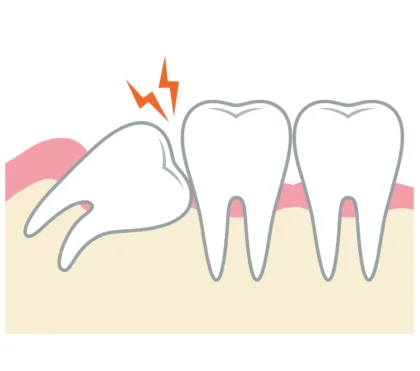

横向き・斜めに生えている親知らず

親知らずがまっすぐに生えておらず、斜めや横向きに生えていると、歯ぐきとの間に汚れがたまりやすくなり、むし歯や歯周病の原因になります。また、隣の歯を押すことで歯並びが乱れたり、他の歯の根が圧迫されてダメージを受けたりすることもあります。

上の親知らずはほっぺた側に傾いて生えてきたり、下の親知らずは横に生えてきて虫歯や部分的な歯周病などを引き起こし、激しい痛みを出したりします。